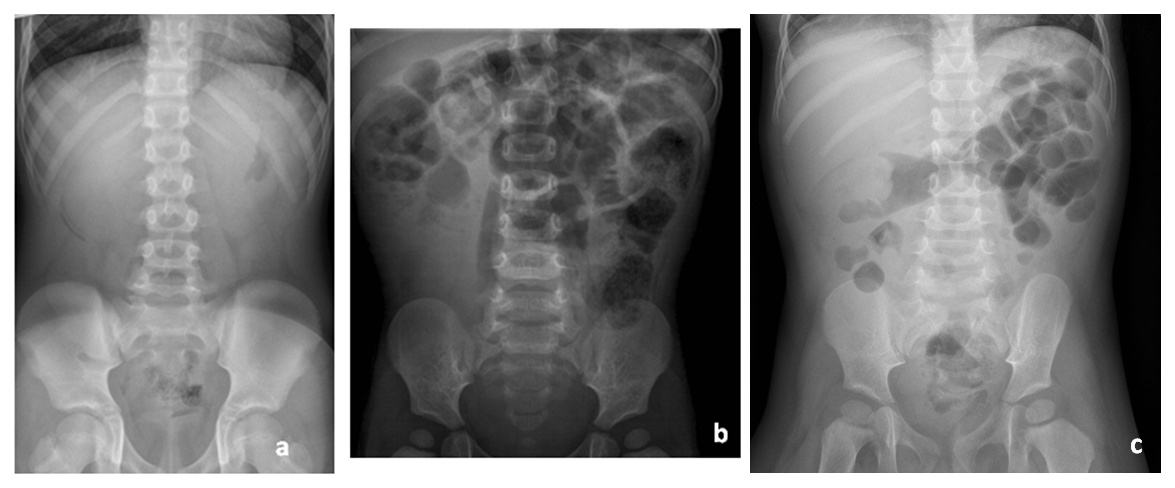

Los pacientes presentan característicamente crisis de dolor abdominal con encogimiento de piernas, seguidas de un periodo de decaimiento. Esto puede ir acompañado de irritabilidad, vómitos, inapetencia y/o deposiciones sanguinolentas (en jalea de grosella)2,3,5,10,13. En el proceso diagnóstico, además de la clínica –que es el pilar principal–, la radiología tiene un papel muy importante. La ecografía, fundamentalmente, y la radiografía simple de abdomen proporcionan imágenes características (en forma de diana, donut o pseudoriñón) (Figs. 1 y2), muy útiles para la identificación de esta patología, así como para su localización y estudio de posibles complicaciones15-20.

| Figura 2. Radiografía de abdomen en pacientes con invaginación intestinal: a) silencio abdominal; b) ausencia de aireación intestinal en flanco derecho; c) cabeza de invaginación intestinal a nivel de ángulo hepático |

|---|

![]() |